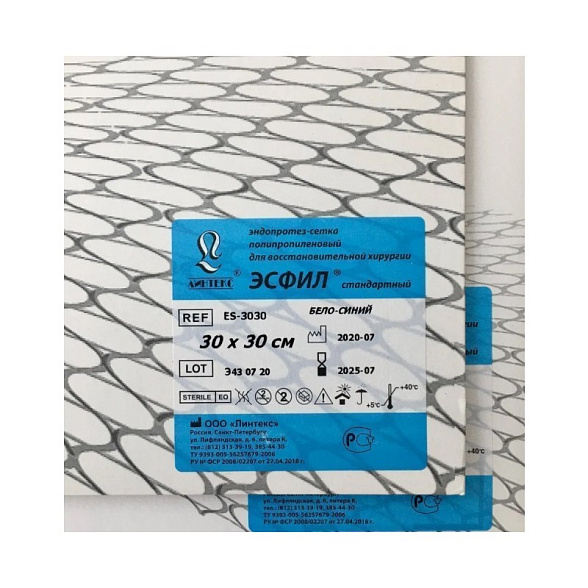

Эндопротез-сетка (сетка хирургическая) полипропиленовый для восстановительной хирургии ЭСФИЛ лёгкий, 20х10 см, Линтекс

Эндопротез-сетка полипропиленовая ЭСФИЛ лёгкий для восстановительной хирургии

| Торговая марка / Бренд | ЭСФИЛ (ESFIL), Линтекс (Lintex) |

| Модель / Тип | Лёгкая (Light) |

| Размеры | 20 см x 10 см |

| Цвет | Белый, синий (может варьироваться в зависимости от партии) |

| Стерильность | Стерильно (как правило, радиационный метод) |